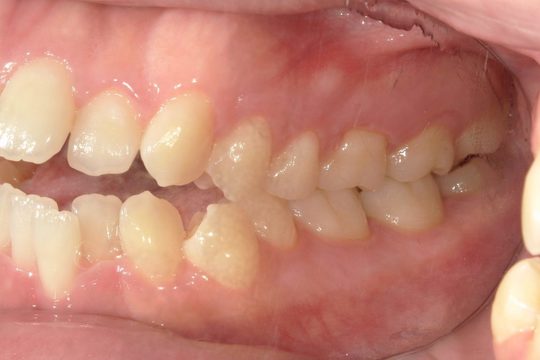

After

浜松市中央区・自動車学校前駅のインビザラインの症例

K.M 20代女性

上の前歯が前方に出ていて横顔が気になるとの主訴でご来院。上下犬歯から犬歯までの6本が噛み合うよう、全体的に歯を内側に移動させることで、前歯の噛み合わせを整え叢生と開咬を治療しました。

​治療の期間:R5. 7/5〜R7. 1/17

​治療の価格:66万円